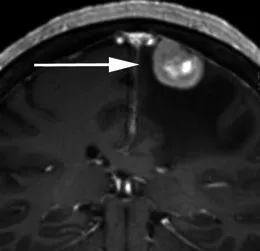

典型脑膜瘤在MRI上呈附着于硬脑膜上的轴外肿块,在T1加权图像上与灰质相比呈等信号或低信号,在质子密度和T2加权图像上呈等信号或高信号,周边有薄层脑嵴液环绕(等信号),表明肿瘤没有侵袭到脑内,通常在使用钆剂后会出现明显而均匀的对比增强。许多脑膜瘤边缘的硬脑膜增厚、向周围逐渐变薄,称为“脑膜尾征”。

一名有1个月精神疾病史的80岁女性的T1加权序列显示,右中颅窝底内有一个界限清楚、均匀增强的肿块,具有宽阔的硬脑膜尾,其下内侧接触右侧海绵窦。右颞叶上方被肿块压迫,但未侵犯。a、b为T2,显示该肿块(箭头所示)呈等灰质信号;c为T1,显示该肿块(箭头所示)呈均匀的轻度高信号(相对于灰质)。